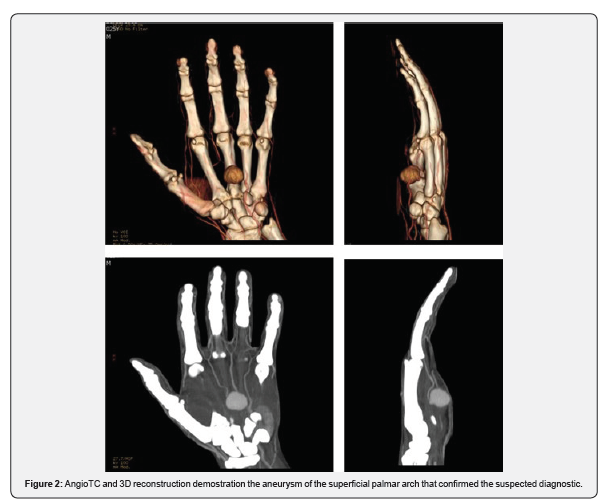

An ECO-Doppler and an angio-CT scan were performed and a pseudoaneurysm of the superficial palmar arch was confirmed (Figure 2). No active bleeding was assessed at this time, and the trophism of the fingers remained normal. Scheduled surgical revision was planned after 48 hours and an excision of the pseudoaneurysm was performed. An end-to-end anastomosis was done with no need for vascular grafts (Figure 3). The piece was sent to histologic examination and the diagnosis was confirmed.